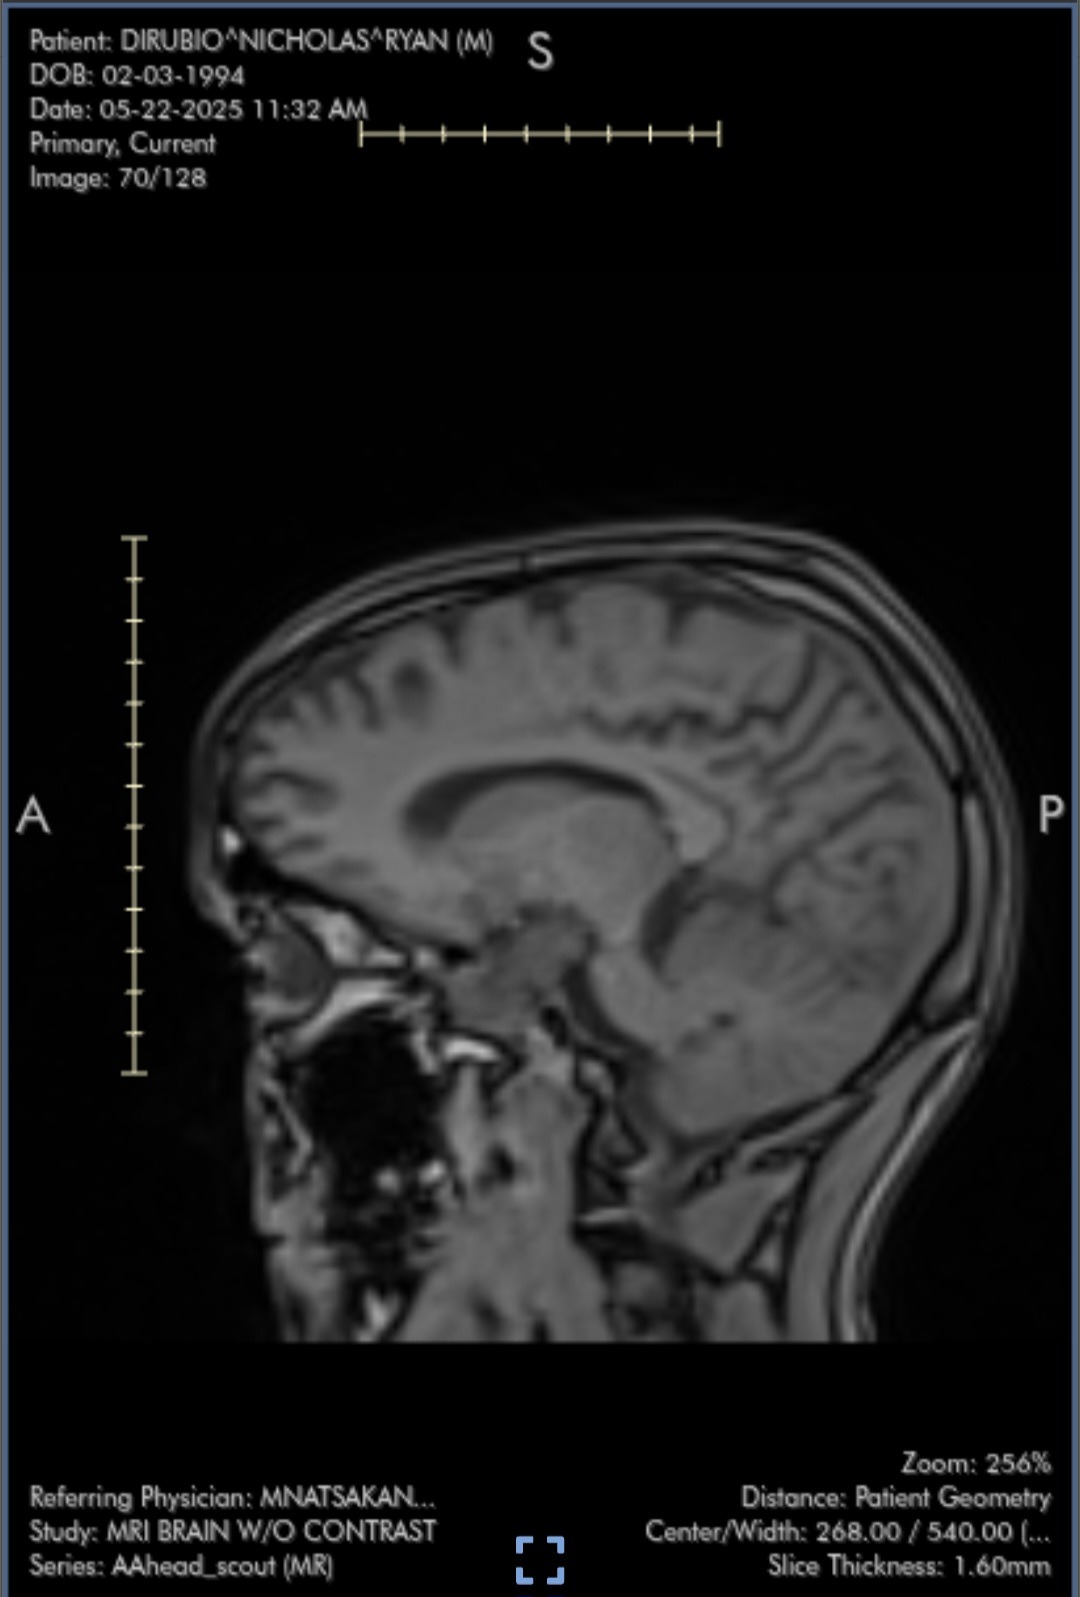

I'm reaching out because on April 15th, I'll be undergoing brain surgery—a life-changing procedure that I never imagined would be part of my story. The news has been overwhelming, and as I prepare for this major step, I'm doing my best to stay hopeful and strong. Facing something so unexpected has been difficult, and I know the road ahead will be challenging, both physically and emotionally.